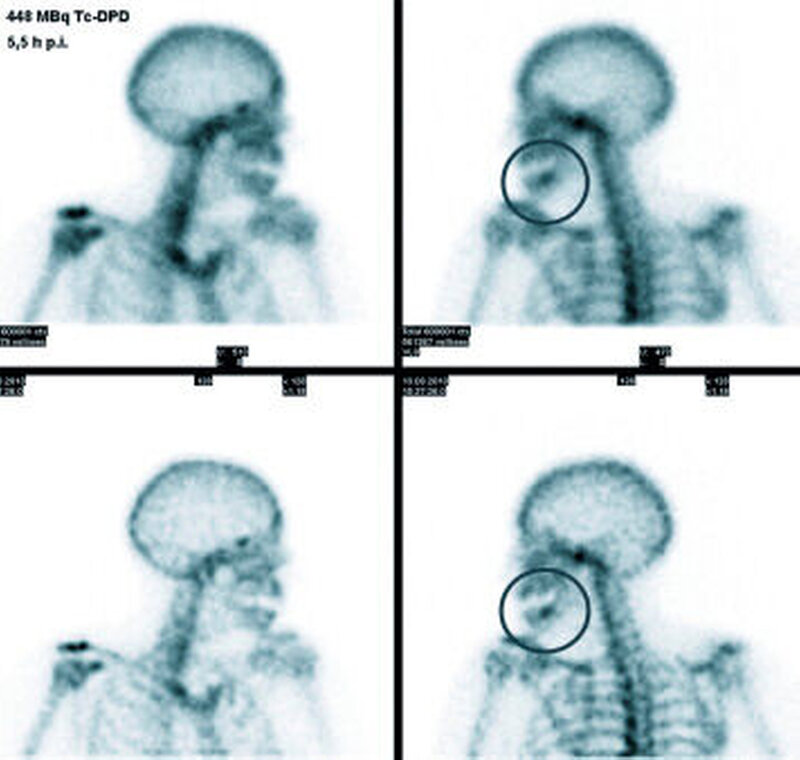

Dreiphasen-Szintigrafie: Die planare Dreiphasen-Szintigrafie mit 99m Tc-markierten Bisphosphonaten ist ein nuklearmedizinisches Standardverfahren in der Diagnose der Kieferosteomyelitis/-nekrose. Sie zeigt die Lokalisation von vermehrtem Knochenumbau (Osteoblastenaktivität) mit hoher Sensitivität an (Abbildung 6). Das Verfahren ist jedoch nicht spezifisch und hat nur eine begrenzte Ortsauflösung [Stockmann et al., 2010].

SPECT(single photon emission computed tomography)-Technik: Die diagnostische Akkuratesse der Szintigrafie kann durch Verwendung der SPECT gesteigert werden (Abbildung 2) [Dore et al., 2009]. Hier werden anders als in der Szintigrafie (in der Aufnahmen aus ventraler und dorsaler Projektion aufgenommen werden) mehrere Aufnahmen aus unterschiedlichen Winkeln akquiriert, aus denen ein dreidimensionales Bild errechnet wird. Dies verbessert die Detektion und die örtliche Zuordnung von fokal vermehrten Traceranreicherungen im Vergleich zu Szintigrafie oder CT allein [Bolouri et al., 2013].